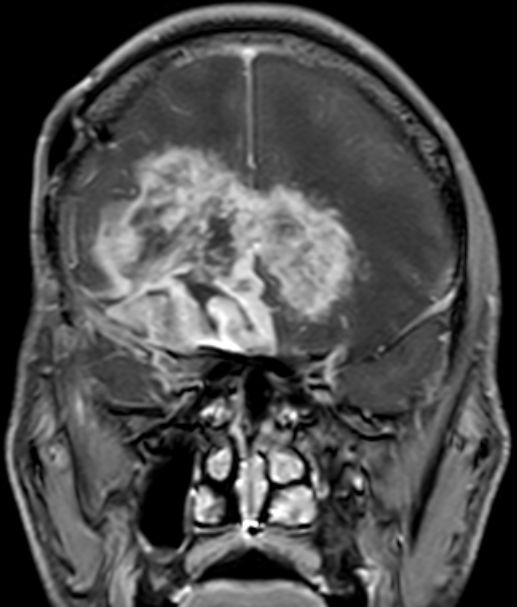

Schmetterlingsgliom des hinteren Balkens |

62-jähriger Mann mit torkeligem Gang, Amnesie und Verwirrtheit. Schmetterlingsgliom des hinteren Balkens.![]() |